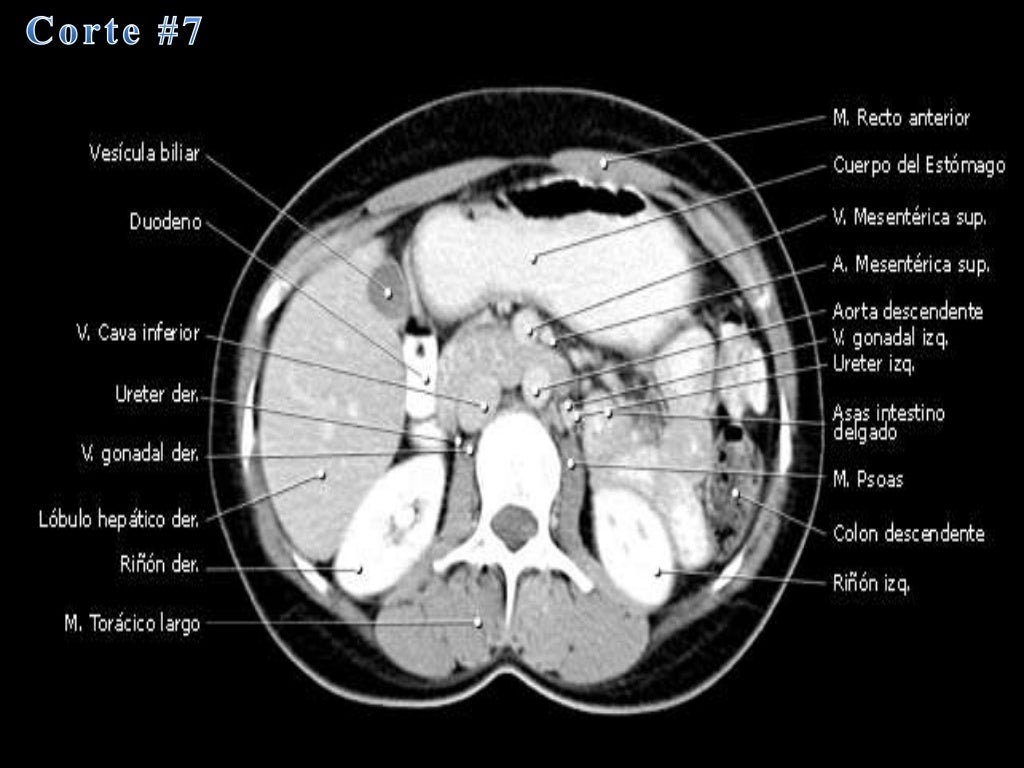

La tomografía computarizada, más comunmente conocida como exploración por tc o tac, es un examen médico de diagnóstico por imágenes.

que es una tomografia abdominal La tomografía computarizada, más comunmente conocida como exploración por tc o tac, es un examen médico de diagnóstico por imágenes. La angiotomografía computarizada del corazón es una forma útil de detectar arterias coronarias obstruidas. Una tomografía computada abdominal utiliza una máquina especial de rayos x para tomar imágenes del hígado, bazo, riñones, vejiga, estómago, intestinos, páncreas y glándulas. Una tomografía de abdomen es un estudio de imagen que ayuda a detectar problemas de salud en el área del abdomen. Una tomografía computada abdominal utiliza una máquina especial de rayos x para tomar imágenes del hígado, bazo, riñones,. La tomografía computarizada, tc, es un procedimiento con imágenes que usa equipo especial de rayos x para crear imágenes detalladas, o exploraciones, de regiones. Al igual que los rayos x. La angiotomografía computarizada podría costar menos que una.